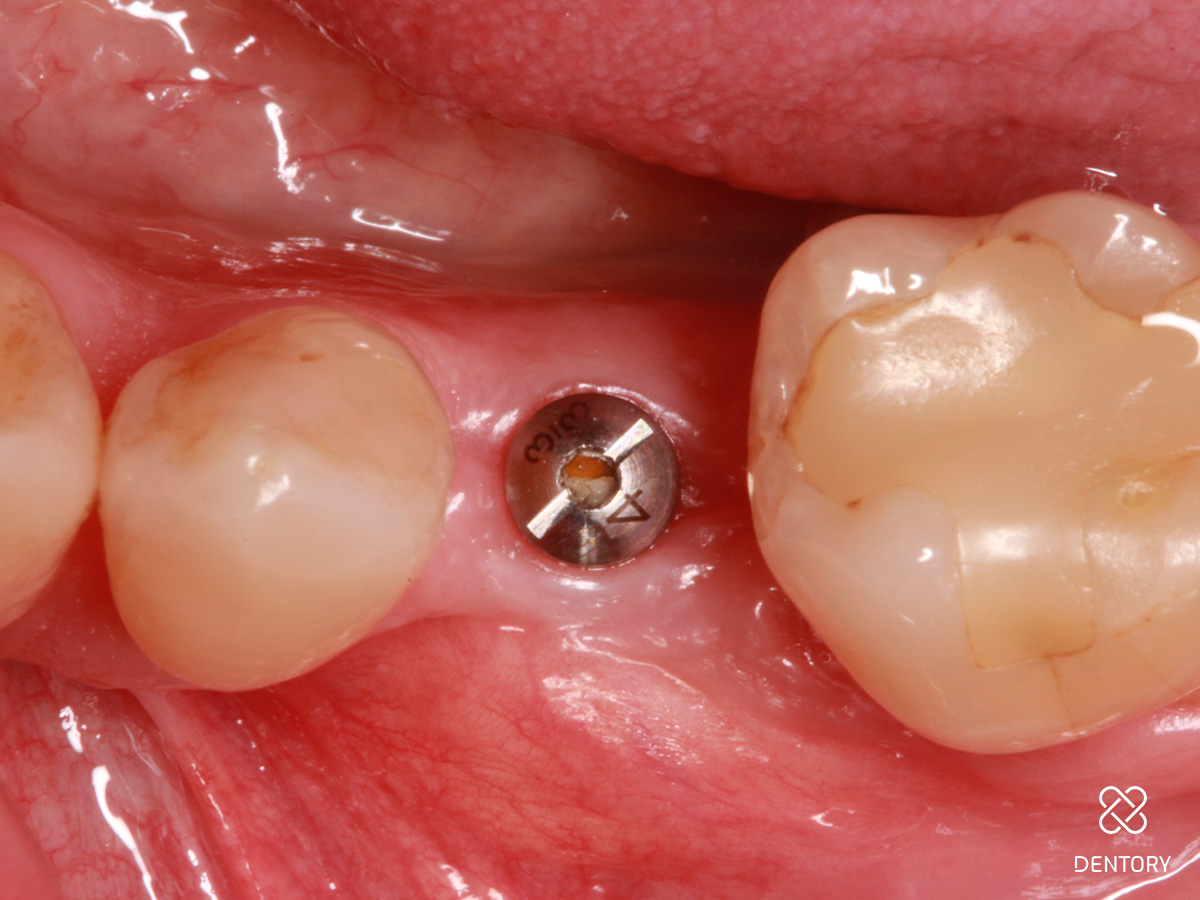

Abbildung 15

Abheilung nach 14 Tagen zum Zeitpunkt der Abformung.

Abbildung 16

Situation vor dem Einsetzen der definitiven Rekonstruktion: Vor dem Einsetzen der definitiven Rekonstruktion zeigen sich gesunde Weichgewebsverhältnisse mit ausreichend befestigter Mukosa für stabile Knochenverhältnisse.